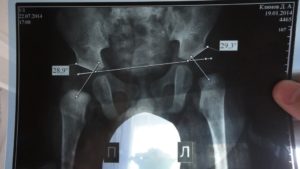

Если тазобедренный сустав имеет связанную с развитием ядра патологию, ее обнаружит УЗИ. Для ее выявления применяют и методы сонографического исследования. Часто может потребоваться и рентгенологическое исследование таза. Рентгеновский снимок для этого выполняется в прямой проекции.

Он дает возможность врачам получать максимально точную информацию о наличии или отсутствии патологии.

Патология ядра выявляется при помощи ультразвукового и сонографического исследования. Дополнительно проводится рентген поврежденных суставов таза. Для рентгеновского снимка выбирается прямая проекция, благодаря чему врачи могут получить более точную и подробную информацию о состоянии опорно-двигательного аппарата ребенка.